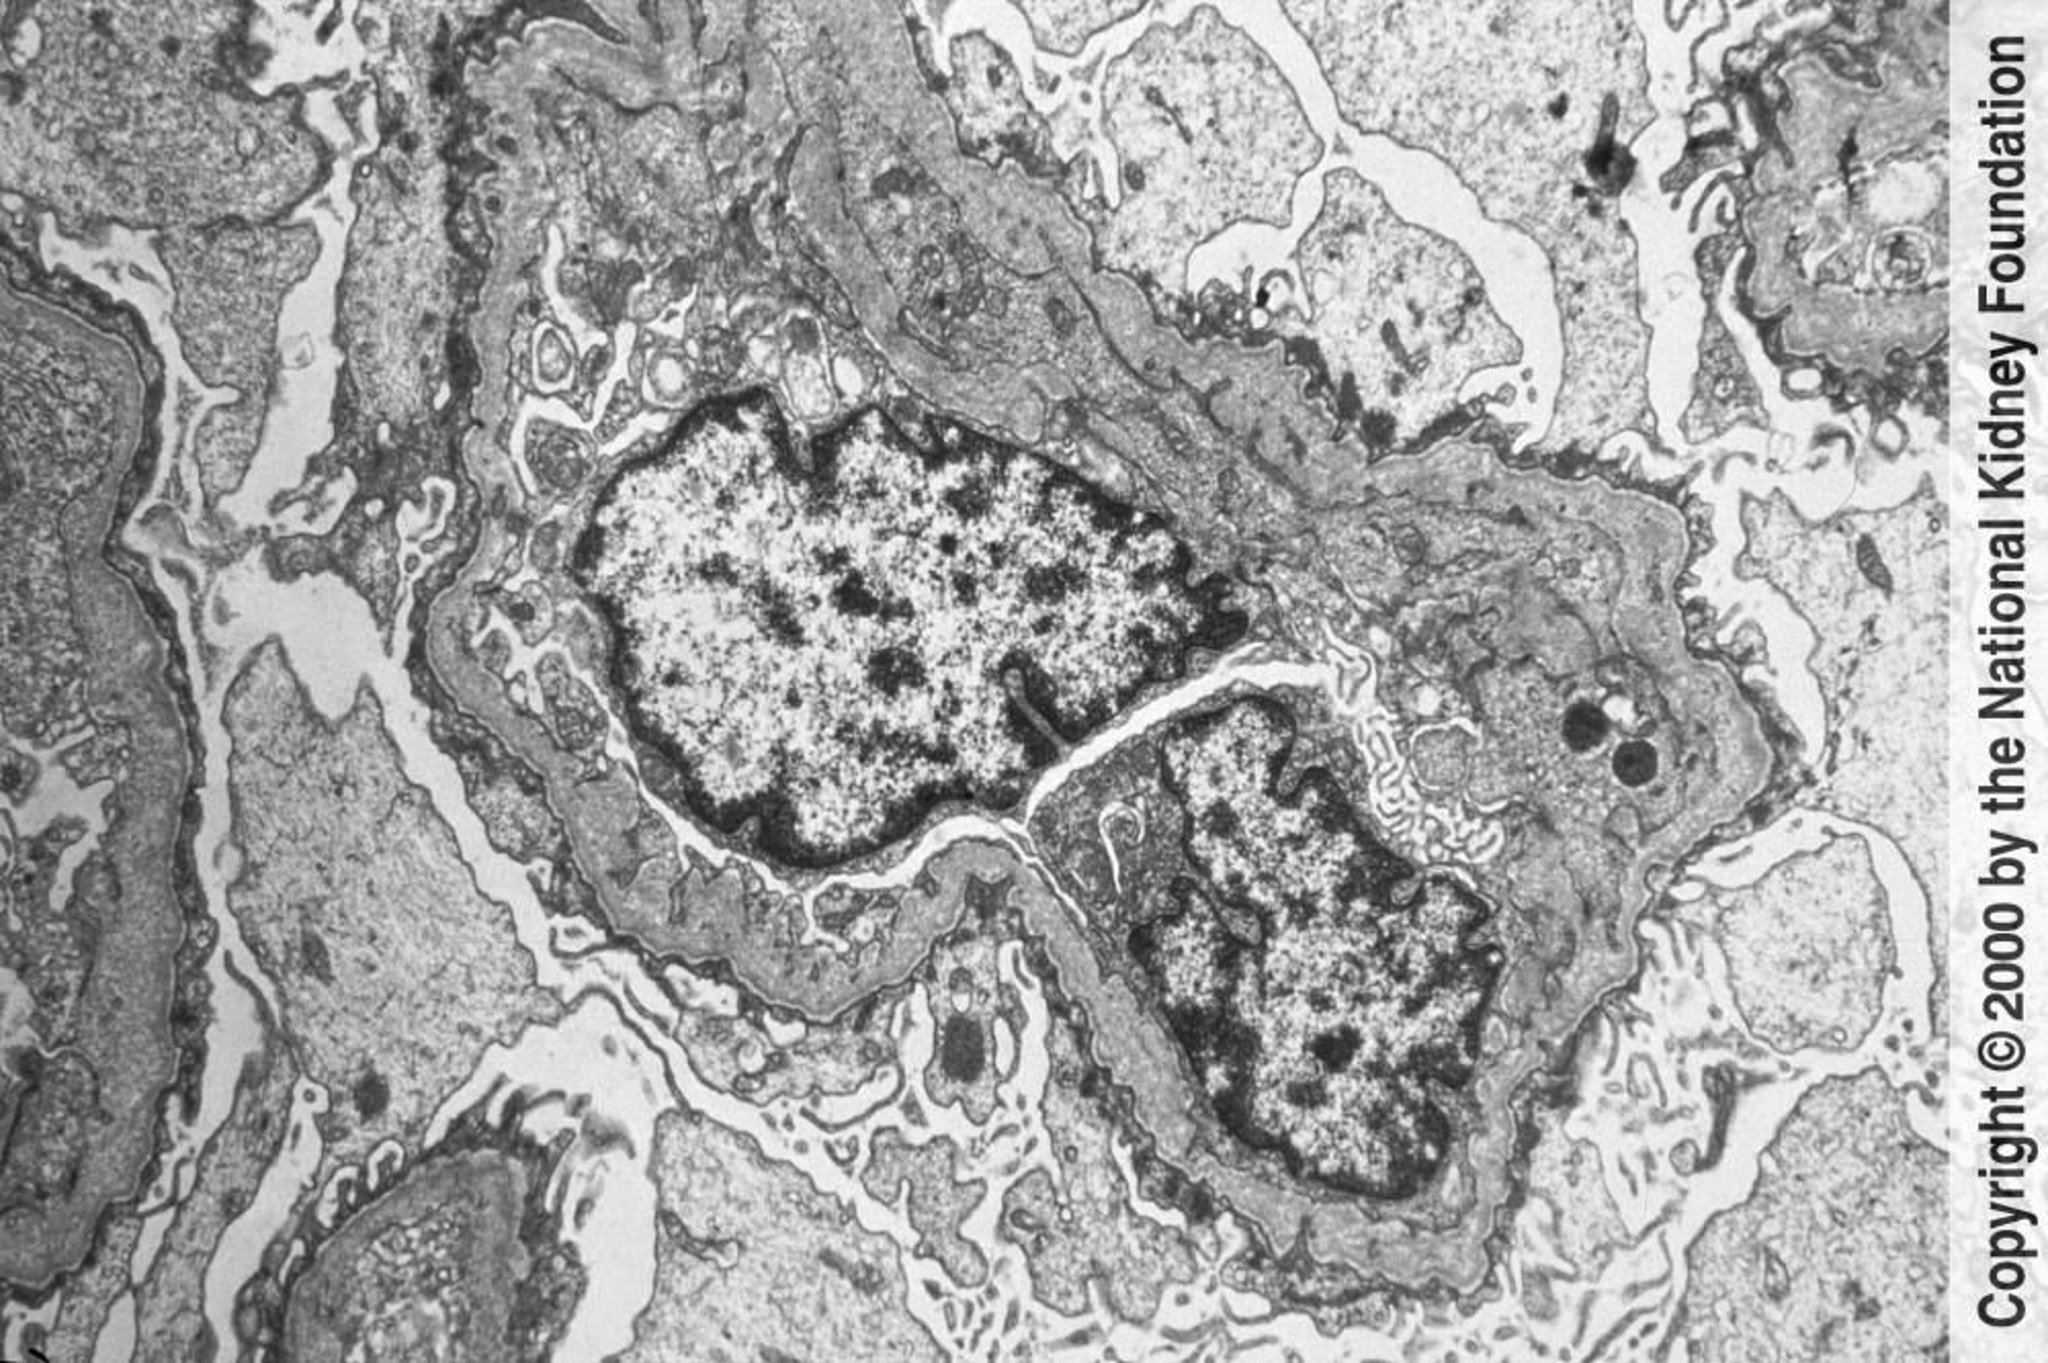

Alport-Syndrom (hereditäre Nephritis)

Die glomerulären Basalmembranen zeigen in der Transmissionselektronenmikroskopie eine unregelmäßige Verdünnung und Verdickung mit einem lamellierten Korbgeflecht. Die Veränderungen werden durch Verletzungen und Umstrukturierungen verursacht (×6000).

Image provided by Agnes Fogo, MD, and the American Journal of Kidney Diseases' Atlas of Renal Pathology (see www.ajkd.org).